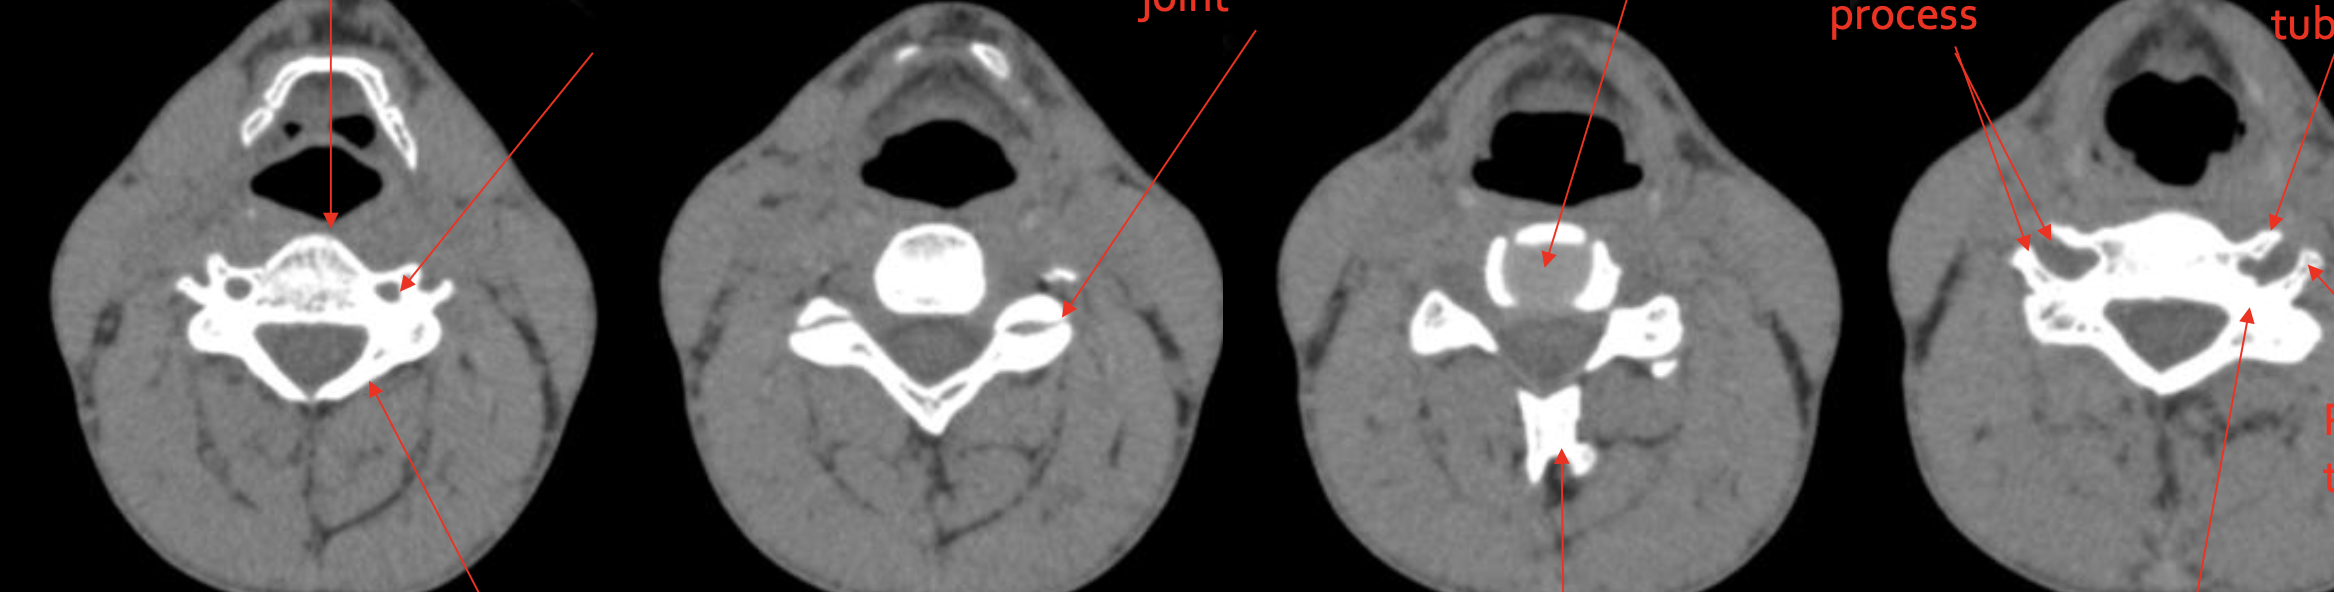

椎体

Vertebral body

椎板

Lamina

关节突关节

Zygapophyseal joint

椎间盘

IVD (Intervertebral Disc)

分叉棘突

Bifid Spinous process